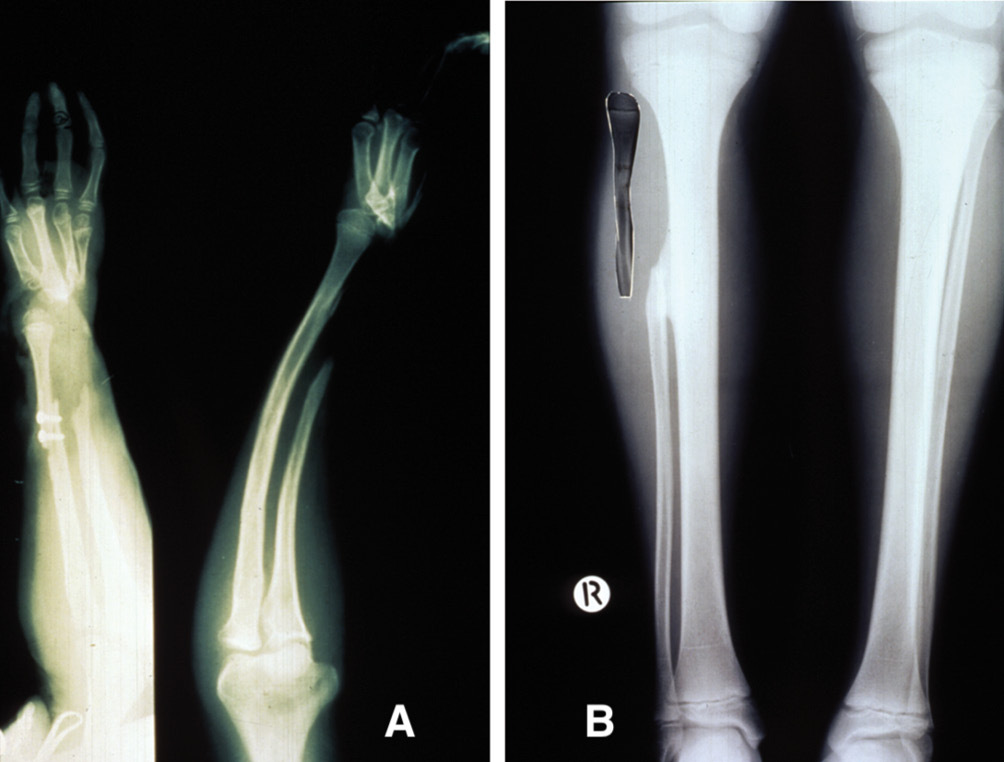

In 1983, a nine-year-old girl presented with a Ewing’s tumour of the right tibial diaphysis (Figure 10 left). She was treated initially with chemotherapy for 12 months with a good result. Segmental resection of the tibia was contemplated and we were invited by Ian Torode and Bob Dickens to consider a fibula reconstruction at the Royal Children’s Hospital Melbourne. Preoperative angiography however, revealed a single peronea magna supplying the foot in the other donor leg. The anterior tibial artery was diminutive (Figure 10 right) but was considered to be of a sufficient size to nourish the fibula transplant.

An 18 cm length of fibula was detached and transferred to bridge the 15 cm defect in the tibia. Periosteum was stripped from the distal end, dowelled into the tibia and secured with a screw. The proximal end was abutted against the underside of the growth plate of the tibia, balanced like a saucer on the end of a pole, and stabilised with an external fixateur (Figure 11A).

At three months the distal end of the fibula graft had united to the tibia. The fixateur was removed leaving behind the transfixing pins that were fixed into an above-knee plaster cast. At eight months the cast was removed, the limb placed in a caliper and weight bearing commenced. Union was noted at the upper end (Figure 11B). By two years dramatic hypertrophy of the transplanted fibula was noted together with growth from the proximal epiphysis (Figure 11C). The limbs had almost identical length (Figure 12), the knee and ankle joints were normal and the only disability was temporary weakness of the EDL in the donor leg.